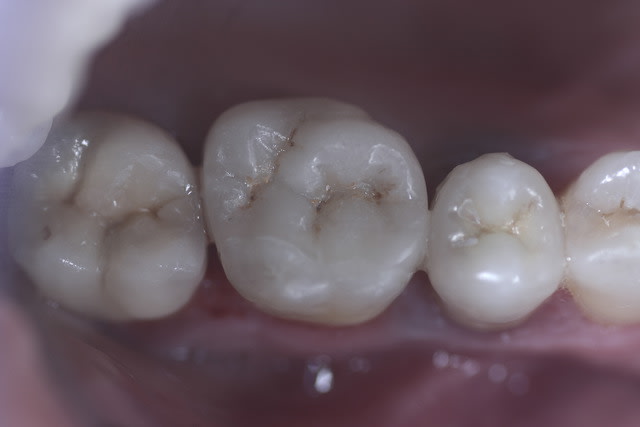

Photo pour mon ami Cingulum

2 p'tites e-max

Très jolies :)